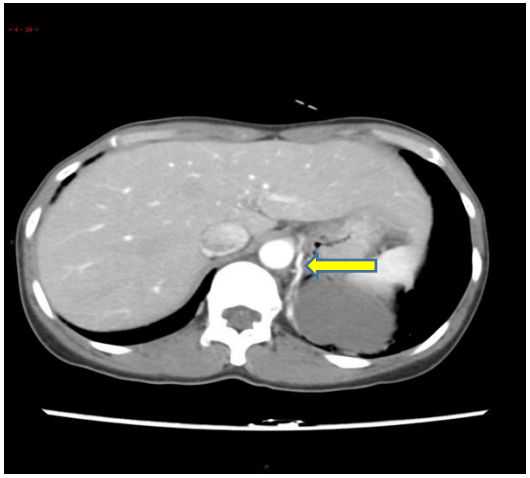

胸部CT扫描检查无痛苦、创伤小,是目前临床上常用的诊断手段。由于低分辨率平扫不能显示异常血管,难以与其他相关疾病鉴别,导致误诊率高,因此,临床上如怀疑肺隔离症,应予以行胸部增强CT+CTA,以准确发现异常滋养血管。

它可以长成这样↓↓↓

图7左下肺内侧基底段团状密度增高影,内可见不规则含气空腔及气液平

也可以仅仅长成这样↓↓↓

图8双肺下叶见少量絮状、磨玻璃样稍,高密度影,边缘模糊